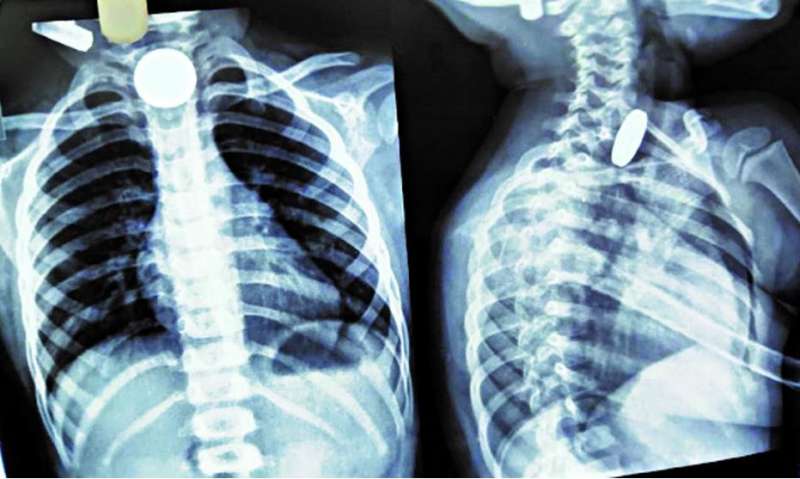

बच्चे को बुधवार देर रात 11 बजे इमरजेंसी में उपचार के लिए लाया गया। बच्चे की एक्सरे जांच में तीन सिक्के खाने की नली में फंसे दिखे। उपचार के लिए तुरंत बच्चे को ऑपरेशन थियेटर लेकर गए। डॉक्टरों की टीम ने एनेस्थीसिया देकर एसोफैगोस्कोपी प्रक्रिया के जरिए सिक्के बाहर निकाले। इसमें दो पांच रुपये के सिक्के और एक दस रुपये का सिक्का शामिल था।